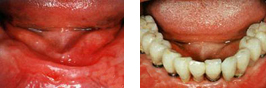

专家诊断:患者口内牙齿大多数长期缺失,缺失牙时间就导致进食、肠胃消化功能受到影响,可引发骨质疏松营养不良问题,所以需要及时做修复。患者牙齿长期的缺失,造成牙槽骨吸收,为了达到固位效果,做传统的活动假牙是不行的。

治疗方案:全口缺失牙的患者不易采取传统假牙,不牢靠,咀嚼度受到影响,还会造成营养不良。对于全口缺失更佳方法是采用种植牙,由于邱女士年纪和经济原因,全口种植牙又昂贵,根据实际情况,做出折中的修复方法是“打桩”(种植牙)+“搭桥”(镶假牙)。

郑州唯美口腔医院赵主任表示,随着口腔医学技术的进步,全口无牙的治疗趋势是:种植牙结合传统的镶牙。种植牙好比在口腔里“打桩”,再在桩上“搭桥”,即镶假牙。这种“种植覆盖义齿”的方法比全口种植牙要经济很多,比传统镶牙要牢固很多,功能也更好。

术后反馈:种植体成功植入,达到了很好的固位效果。再也不用担心说话发音、咀嚼等多方面的问题了,术后患者表示非常满意,感觉自己比以前年轻了很多。